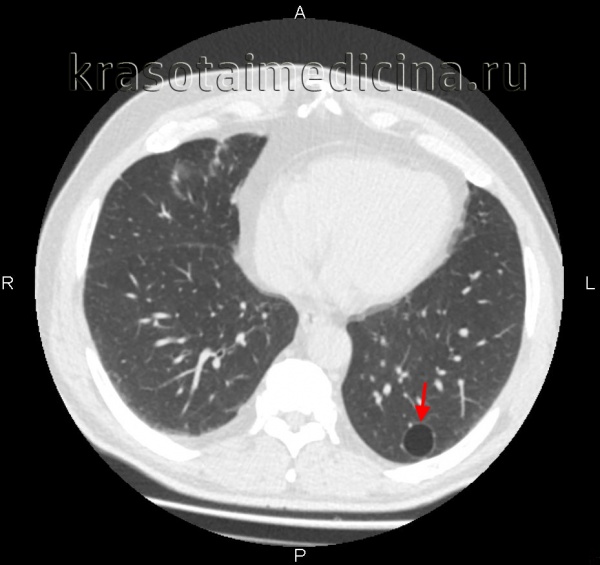

Буллезная эмфизема легкого – это локальные изменения легочной ткани, характеризующиеся деструкцией альвеолярных перегородок и формированием воздушных кист диаметром более 1 см (булл). При неосложненном течении буллезной эмфиземы легких симптомы могут отсутствовать вплоть до возникновения спонтанного пневмоторакса. Диагностическое подтверждение буллезной эмфиземы легких достигается с помощью рентгенографии, КТ высокого разрешения, сцинтиграфии, торакоскопии. При бессимптомной форме возможно динамическое наблюдение; в случае прогрессирующего или осложненного течения буллезной болезни легких проводится хирургическое лечение (буллэктомия, сегментэктомия, лобэктомия).

Диагностика буллезной эмфиземы легких основывается на клинических, функциональных и рентгенологических данных. Курация больного осуществляется пульмонологом, а при развитии осложнений – торакальным хирургом. Рентгенография легких не всегда эффективна в выявлении буллезной эмфиземы легких. В то же время, возможности лучевой диагностики существенно расширяет внедрение в практику КТ высокого разрешения. На томограммах буллы определяются как тонкостенные полости с четкими и ровными контурами. При сомнительном диагнозе удостовериться в наличии булл позволяет диагностическая торакоскопия.